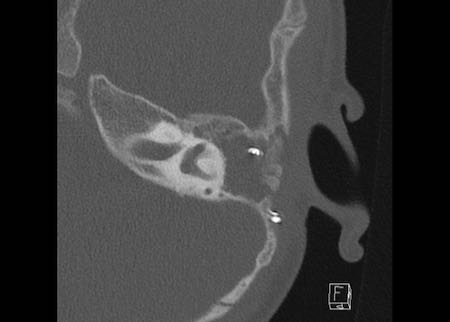

Bên trái là hình ảnh của một bé gái 2 tuổi.

Các hình ảnh từ kết quả chụp CT được thực hiện trước khi cấy ốc tai điện tử.

Quan sát thấy dị dạng nhẹ ở đỉnh ốc tai – không có sự phân tách giữa vòng thứ hai và vòng thứ ba, và trụ ốc tai xương vắng mặt.

Cống tiền đình bình thường.